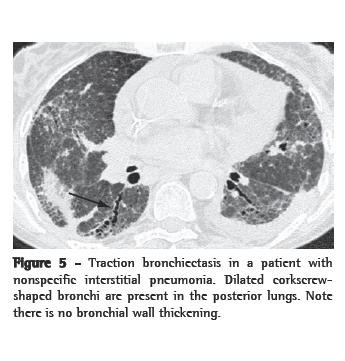

Traction bronchiectasis

Bronchial dilatation occurring as a consequence of interstitial fibrosis is referred to as traction bronchiectasis (Figure 5). The bronchi often appear irregular (corkscrewed) and are not associated with radiologic evidence of bronchial inflammation (gross bronchial wall thickening or mucous impaction). Traction bronchiectasis is often accompanied by other signs of lung fibrosis (honeycombing or irregular reticulation). While traction bronchiectasis is quite specific for fibrosis, the differential diagnosis is broader than that of honeycombing. Idiopathic pulmonary fibrosis (IPF) is commonly associated with traction bronchiectasis. However, in the absence of honeycombing, other diseases are more likely (Chart 3). In patients with known collagen vascular disease, bibasilar, peripheral, traction bronchiectasis accompanied by ground-glass attenuation can be considered diagnostic of NSIP. When the circumstances are less diagnostic, a surgical biopsy might be required.